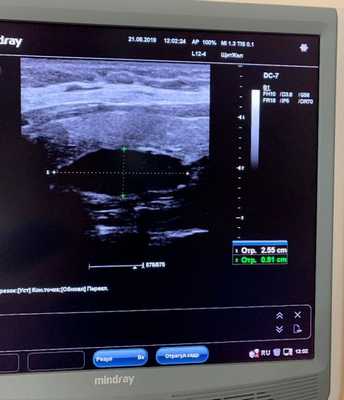

1. Ультразвуковое исследование

Исследуемая область при УЗИ сверху ограничена бифуркацией (разделением) сонной артерии, снизу — грудинной вырезкой, сбоку — сонной артерией/внутренней ярёмной веной [7] . Паращитовидные железы нормального размера обычно не визуализируются с помощью ультразвука. Аденомы проявляются в виде овальных анэхогенных (выглядят чёрными) или гипоэхогенных (выглядят тёмно-серыми) образований, расположенных кзади от щитовидной железы. Обычно можно увидеть эхогенную (светлую) линию, которая отличает щитовидную железу от увеличенной паращитовидной железы. Более крупные аденомы чаще имеют кистозные изменения.